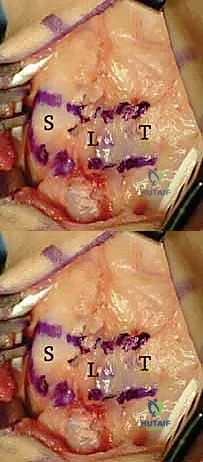

While primary repair is crucial, the native SLIL is inherently slow to heal, and the repair is subjected to immense shear forces. Therefore, we augment the repair with a dorsal capsulodesis, utilizing the previously elevated ulnar-based capsular flap (a modification of the classic Blatt capsulodesis) or a slip of the DIC ligament.

The ulnar-based dorsal capsular flap is prepared for augmentation. It will act as a secondary dorsal tether, reinforcing the primary SLIL repair.

The distal end of our capsular flap is advanced distally and radially across the repaired SL joint. A trough is created on the dorsal aspect of the distal scaphoid pole. Another suture anchor is placed into this trough.

The capsular flap is advanced and secured to the distal scaphoid using an additional suture anchor. This effectively tethers the scaphoid, preventing it from falling back into a flexed posture.

By securing the capsular flap to the distal scaphoid, we create a stout dorsal check-rein. This capsulodesis neutralizes the inherent flexion forces acting on the scaphoid, offloading the primary SLIL repair during the critical early phases of biological healing.